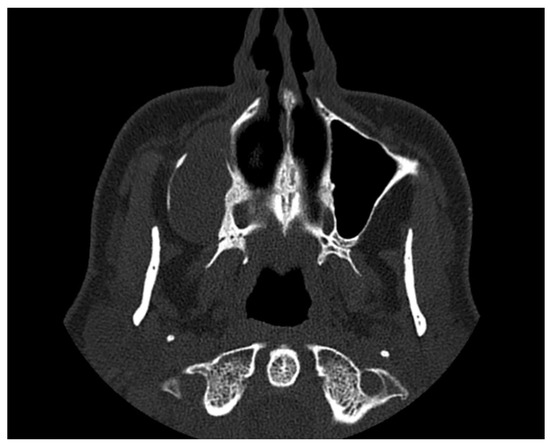

2. Case Presentation